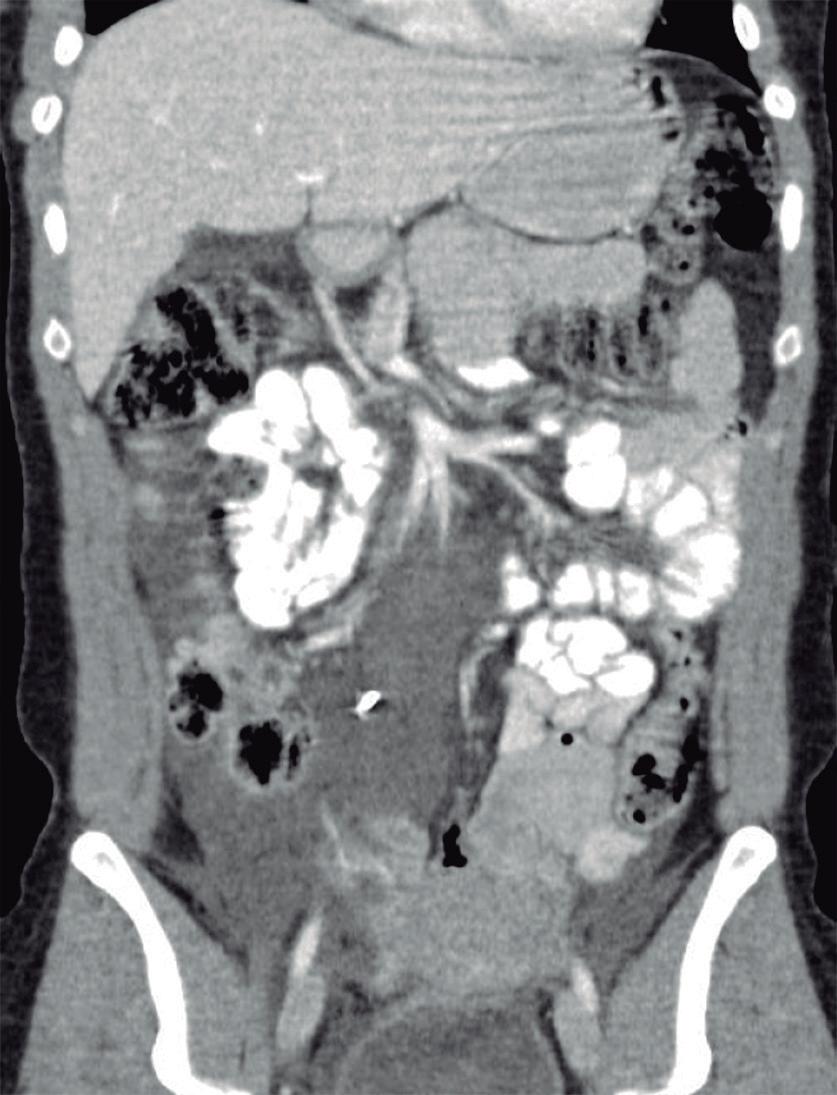

Evaluación endoscópica e histológica

La endoscopía superior es un procedimiento fundamental para el diagnóstico, la evaluación de la respuesta al tratamiento y el monitoreo a largo plazo de la actividad de la EEo. Los hallazgos endoscópicos típicos incluyen edema (reducción de vascularidad), anillos esofágicos fijos, exudados blancos, surcos longitudinales, estenosis, estrechamiento de la luz esofágica, friabilidad de la mucosa (mucosa en papel crepé) y una consistencia firme de la mucosa al realizar biopsias (signo de “tracción" o "resistencia”) en pacientes con fibrosis (Figura 1). Estos hallazgos no son patognomónicos y no constituyen un criterio diagnóstico; sin embargo, cuando se evalúa de forma cuidadosa, en la gran mayoría de los casos se pueden observar.19-21

En el panel A se observa un esófago con edema difuso y pliegues longitudinales; en el panel B se aprecia edema con pliegues y exudados blanquecinos; en el panel C se evidencia un estrechamiento luminal acompañado de anillos esofágicos y exudados; y en el panel D se muestra un desgarro mucoso posterior a la dilatación con bujía de Savary, hallazgo esperado tras este procedimiento terapéutico.

Figura 1. Características endoscópicas de la esofagitis eosinofílica